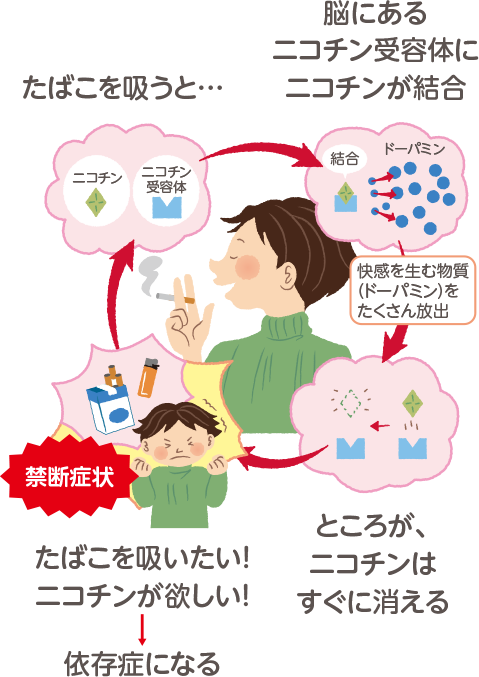

禁煙の医学 禁煙は愛 禁煙推進webサイト

禁煙教育 の部屋へようこそ

禁煙の医学 禁煙は愛 禁煙推進webサイト